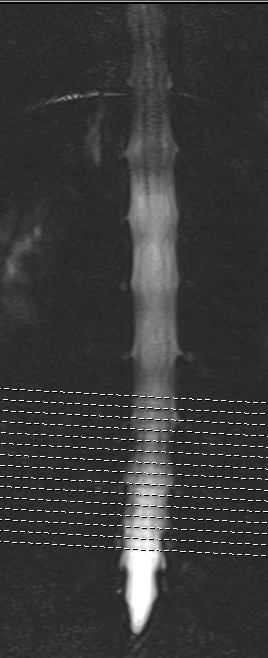

Mittlerweile hatte ich mit einigen teils schwerwiegenden Erkrankungen zu kämpfen, zu denen sich seit kurzem verschiedene neurologische Symptome, Rückenschmerzen, Mißempfindungen etc. dazugesellten. Ich wurde zum Rücken-MRT (vom Neurologen) geschickt wegen Verdacht auf eine entzündliche Erkrankung des ZNS. Leider wurde aus Abrechnungsgründen statt der gesamten WS nur die LWS gemacht. Hier kam heraus, dass sich die Skoliose auf 16 Grad mehr als verdoppelt hat. Außerdem kam wohl eine Hyperlordose 15 Grad?? dazu. Die Aufnahme von vorn sieht jedenfalls ziemlich krumm aus. Wie der Rest meiner WS aussieht weiß ich leider nicht

Zusätzlich multiple Schmorlsche Wirbelknoten, welche es vor 6 Jahren noch nicht gab... leider kann ich nur ein Bild anhängen, die anderen bekomme ich iwie nicht als jpg. gespeichert...

Der Radiologe sagt alles normal, sei ein alter Scheuermann... aber den hätte man doch sicher vor 6 Jahren schon erkannt, auf den alten Bildern sieht alles schön sauber aus, auf den neuen naja ich weiß nicht... irgendwie schon anders oder was meint ihr...? Kann man auf dem Bild etwas sehen ob wirklich alles ok ist? Und wenn nicht, was kann ich dagegen tun? KG alleine scheint nicht sehr effektiv zu sein?